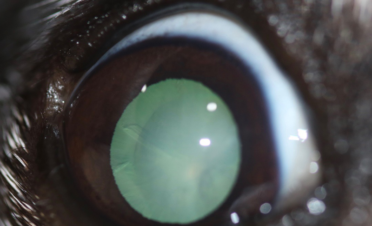

Miso es una hembra de Jack Russell de 12 años de edad que acudió a IVO para una primera valoración de cataratas bilaterales.

Sus propietarios habían notado un inicio de catarata en el ojo izquierdo hacía un año y medio aproximadamente, y en los últimos dos meses pérdida de visión por la noche y durante el día, coincidiendo con la aparición de una catarata en el ojo derecho.

En el caso de Miso, la catarata del ojo derecho estaba más desarrollada que la del izquierdo, pero se operaron ambas el mismo día para que su recuperación fuera más rápida y solo tuviera que pasar por quirófano una vez.